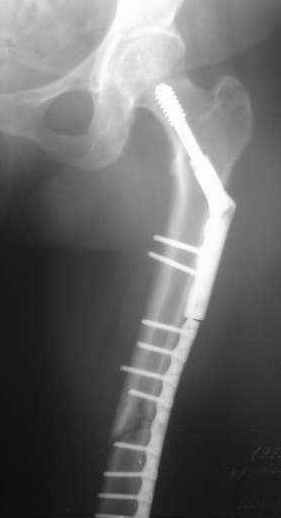

Сегодня мною была осмотрена больная, которой я выполнил накостный остеосинтез около четырех месяцев назад по поводу фрагментарного перелома бедра на уровне средней трети и межвертельной зоны.

Перелом синтезированный DHS сросся, а вот на уровне средней трети - нет. И, похоже, есть нехорошая тенденция к резорбции.

Больная 47 лет, поступила в отделение после автодорожной травмы от 08 июля сего года с DS: ЗЧМТ, СГМ. Закр. чрезвертельный перелом и перелом с/3 левого бедра со смещением. Ушиб и рваная рана левого коленного сустава. Соп.: Хр. железодефицитная анемия. (Гемоглобин при поступлении 71 г/л). 08 июля - ПХО ран колена.

11 июля остеосинтез бедра DHS + LC DCP.

Я выкладывал на Форум этот случай, где высказывались опасения, что не исключается варусная дислокация межвертельного перелома на фиксаторе из-за малой длины Screw ... вроде пронесло ... перелом сросся. Но маленькая

победа в отдельной битве, все же не принесла победы в целом... Остается неопорная конечность, ограничение движений в коленном суставе 180 - 150 град., отечность голени и стопы, по-видимому, из-за сосудистой недостаточности, гипотрофии